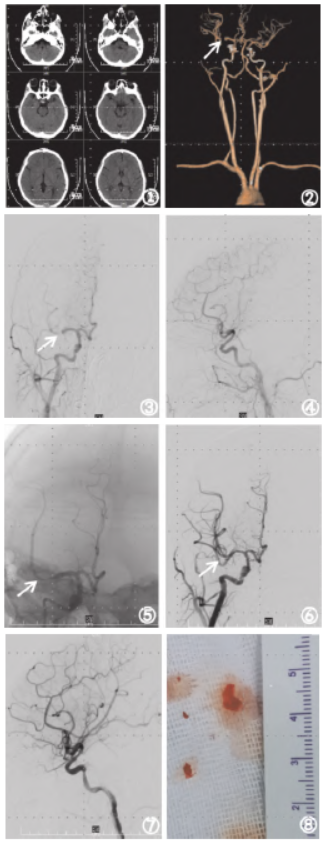

示窦性心律。头颅CT示颅内未见明显异常(图1 ①);头颈部CTA 示右侧大脑中动脉闭塞(图1 ②③)。

、大脑中动脉闭塞;高血压病。在充分告知家属手术必要性及相关风险并取得书面同意后,决定立即对该患儿实施血管内介入手术。全身麻醉后,选择右侧股动脉穿刺,置入8F股动脉鞘(泰尔茂,规格:RF*GA35153M),5F 造影导管(埃普特,规格:管径范围5F,长度范围100cm)进行全脑血管造影

提示:右侧大脑中动脉M1段存在闭塞现象,而大脑前动脉、颈外动脉以及大脑后动脉未显示出显著的代偿性血流供应。

将8F导引导管(康蒂思,规格:588842P)超选至右侧颈内动脉C1段,5F115cm 颅内支撑导管(璞慧医疗,规格:PH-GC-02-01)超选至颈内动脉海绵窦段,0.014in微导丝(美科微先,规格:GW1420040)引导下将Rebar18微导管(EV3)超选至大脑中动脉M2段,经微导管将4mm~20mm 取栓支架(尼科医疗,规格:RVV-I-4-20)缓慢释放,完全退出微导管,4min后收回支架,持续抽吸颅内支撑导管,取出较硬白色血栓,成功开通闭塞血管,血流mTICI分级3级,即刻头颅CT 未见造影剂外渗。

手术完成后,患者被转送至重症监护病房接受进一步治疗。术后20小时复查头颅CT 和头颈部CTA 提示:颅内未见大面积脑梗死及出血转化,颅内血管通畅。术后26小时停用镇静药物,患儿苏醒拔除气管插管。术后第5天患儿NIHSS评分为0分,mRS评分为0分,康复出院。

图1 患者诊疗过程中影像资料①头颅CT检查

示:颅内无出血及大面积脑梗死;②头颈部CTA检查示:Ⅰ型弓,右侧大脑中动脉M1段闭塞;③、④右侧颈总动脉正侧位造影提示:右侧大脑中动脉M1段分叉部闭塞,颈外动脉及大脑前动脉无明显代偿供血;⑤Reco取栓装置释放后右侧大脑中动脉前向血流恢复;⑥、⑦支架取出后,血管再通,血流mTICI分级3级;⑧取出的栓子;⑨栓子镜检为机化的血栓,其内见个别退变的细胞影;⑩取栓术后20小时复查头颅CT未见出血转化及大面积脑梗死。